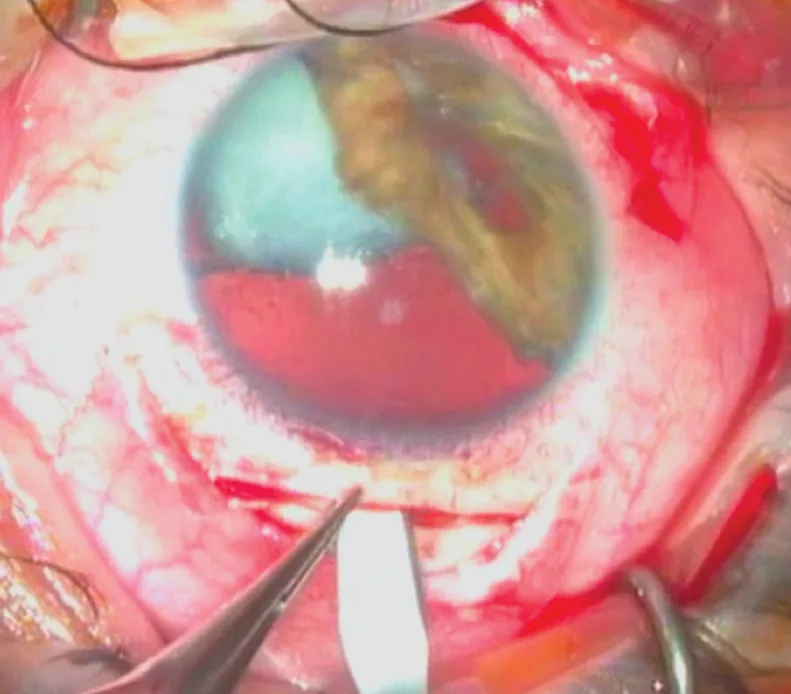

Figure 3.1 S’ouvre dans une nouvelle fenêtre . Incision sclérale : phase de tunnélisation au couteau de Crescent.

Figure 3.1 . Incision sclérale : phase de tunnélisation au couteau de Crescent.

Les incisions cornéennes transfixiantes, voies d’abord et première étape de la chirurgie conventionnelle de la cataracte, conditionnent la qualité du geste chirurgical, mais aussi le résultat réfractif final. Il existe plusieurs façons de réaliser ces incisions en termes de localisation, d’axe, de dimensions et de construction. En pratique, les incisions en cornée claire ont progressivement remplacé les incisions sclérales (figure 3.1 et vidéo 9 ) [1] .

Aujourd’hui, ces dernières sont indiquées uniquement en cas d’altérations importantes de la cornée périphérique, soit primitives, comme les fontes stromales séquellaires périphériques, soit post-chirurgicales comme les kératoplasties transfixiantes de grand diamètre, les kératotomies radiaires serrées ou encore les capots de laser in situ keratomileusis (LASIK) décentrés. La largeur des incisions a progressivement diminué, pour s’établir actuellement entre 1,7 mm et 2,2 mm en chirurgie coaxiale (vidéo 9, cas 3 et 4), et entre 1 mm et 1,6 mm en chirurgie bimanuelle (vidéo 9 , cas 2 ). Ainsi les objectifs de sécurité, d’innocuité et de résultat réfractif ont progressivement façonné les incisions cornéennes d’aujourd’hui.